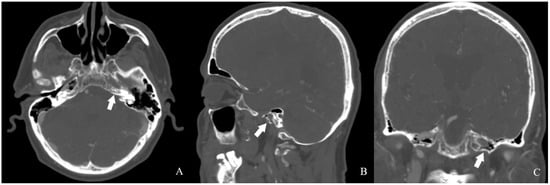

A review of the patient’s radiologic records revealed a cranial CT angiography performed nine years ago. Imaging showed no contrast in the left internal carotid artery. In addition, the left petrosal carotid canal was found to be intact (Figure 5 and Figure 6).

Figure 6.

The patient’s CTA images [(A) axial, (B) sagittal, (C) coronal] revealed a preserved carotid canal [white arrow].

3. Results

CT imaging demonstrated a well-developed carotid canal, strongly favoring the diagnosis of chronic ICA occlusion rather than congenital agenesis. This underscores the importance of assessing the carotid canal in differentiating between these two entities. At the time of the patient’s initial presentation, MR angiography performed in our clinic suggested ICA agenesis, as there was no history of recurrent ischemic events. However, review of prior imaging revealed a CT angiography obtained nine years earlier, which confirmed the diagnosis of ICA occlusion. Given the evidence of a patent carotid canal, MR-VWI was deemed unnecessary. Although surgical or endovascular treatment was advised, the patient declined intervention and opted for continued clinical surveillance. During the current presentation, antiplatelet therapy and symptomatic medical management were initiated in the outpatient setting, resulting in clinical improvement at 3 months of follow-up (VAS score: 2, TFI grade: 1). The patient was again counseled regarding the risks associated with chronic ICA occlusion, including the elevated risk of ischemic stroke, and revascularization strategies, including hybrid procedures (combining STA–MCA bypass with endovascular techniques in a single session), were once more discussed.